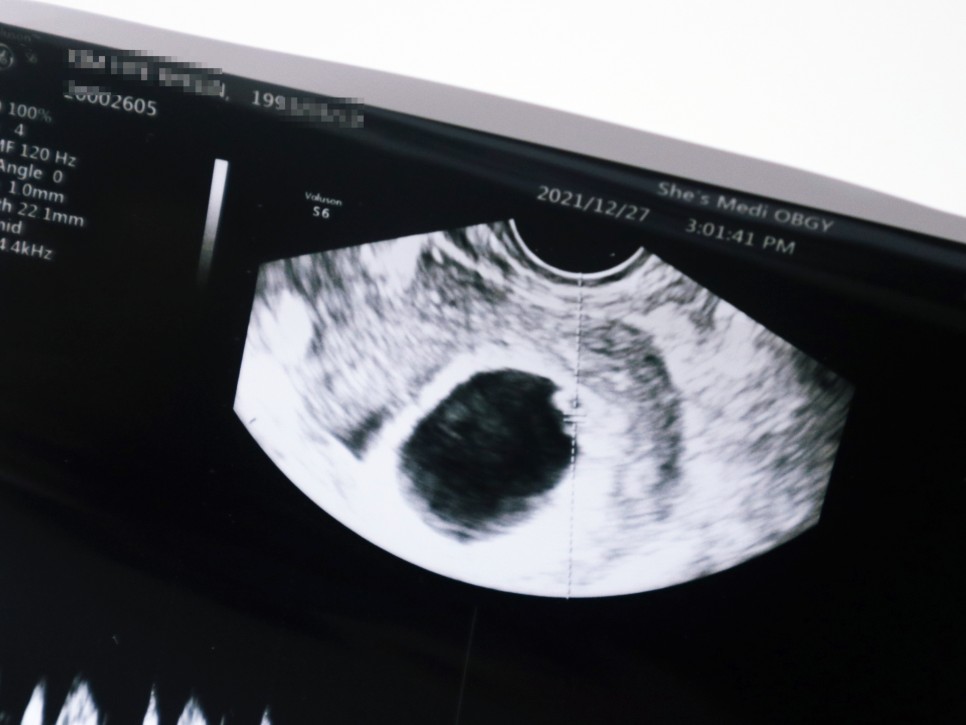

임신 7주 0일(21년 12월 27일) 임신 7주차 태아 심박수 태아 소견 신장 0.9cm

임신 4주 5일 첫 방문 때 0.2cm 아기집을 봤는데 정작 태아는 보지 못했어요.그래서 이날은 아기 집에 두루치를 확인하고 심박수를 체크하는 날이었어요.임신 7주 차 초음파상 아기의 집도 매우 커지고 있었는데, 그 안에서 젤리 아기를 발견할 수 있었습니다. 노른자도 꼭 확인했어요.선생님이 보시면 넓은곳이 많은데 저위에 붙어있다고 ㅋㅋㅋㅋ

임신 초기에 엽산과 비타민D를 잘 먹으라는 말씀과 소량의 피의 비침은 괜찮지만 생리혈처럼 쏟아져 나오는 증상이 있으면 바로 내원하라고 말씀하셨습니다.아기 심장 박동수도 굿굿!!!